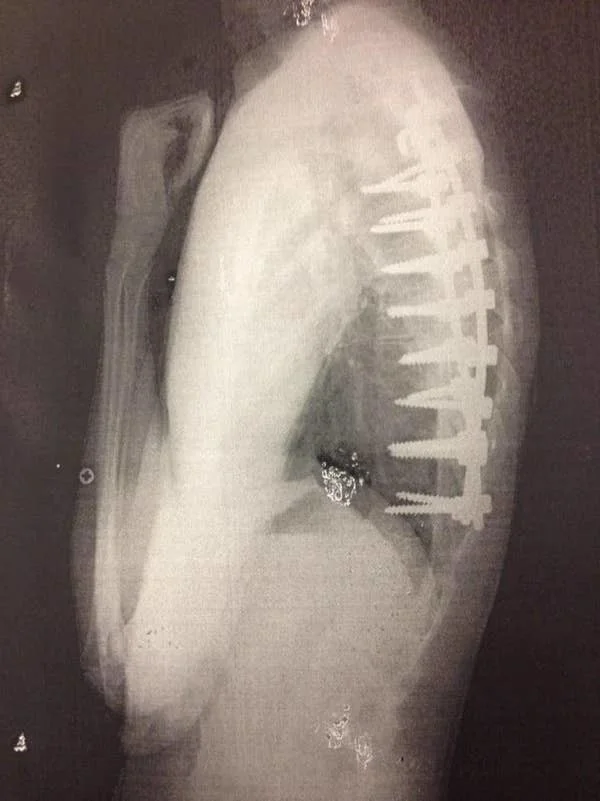

34. Для меня до сих пор дико, что в ходе операций на позвоночнике используют винты